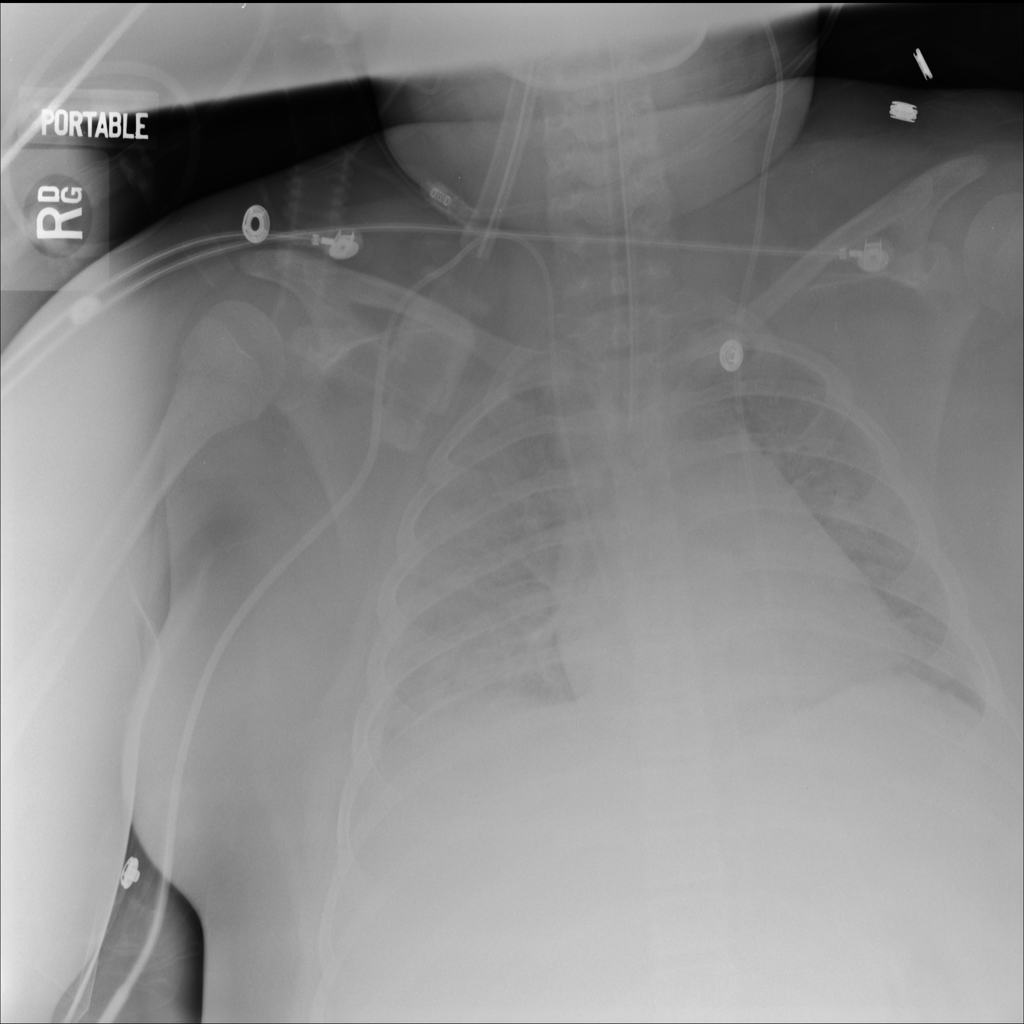

PAT-24D9 · IMG-006Edema

PAT-24D9 · IMG-006

AP